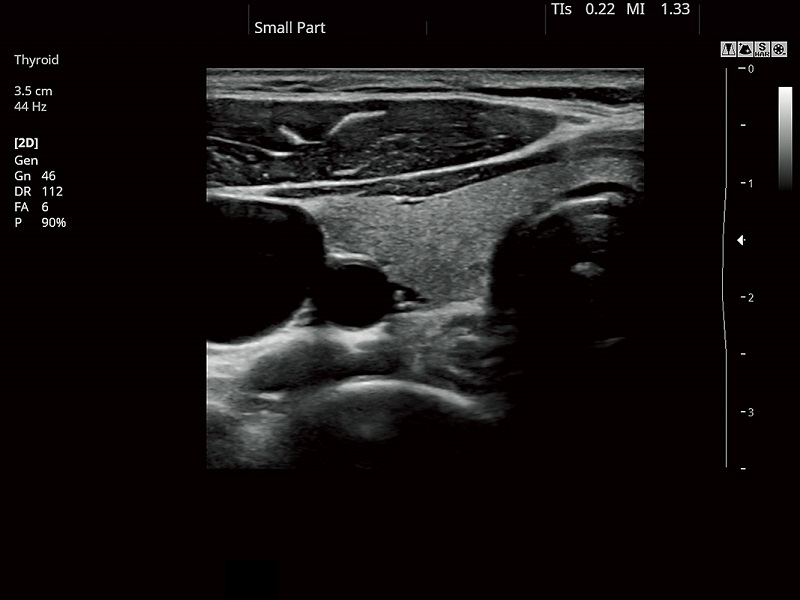

FUTUS features great imaging technologies to support a clear view and confident diagnoses.